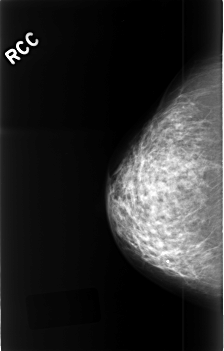

C_0419_1.RIGHT_MLO

C_0419_1.RIGHT_CC

RIGHT_CC LINES 4552 PIXELS_PER_LINE 2912 BITS_PER_PIXEL 12 RESOLUTION 50 NON_OVERLAY

RIGHT_MLO LINES 4560 PIXELS_PER_LINE 2888 BITS_PER_PIXEL 12 RESOLUTION 50 NON_OVERLAY